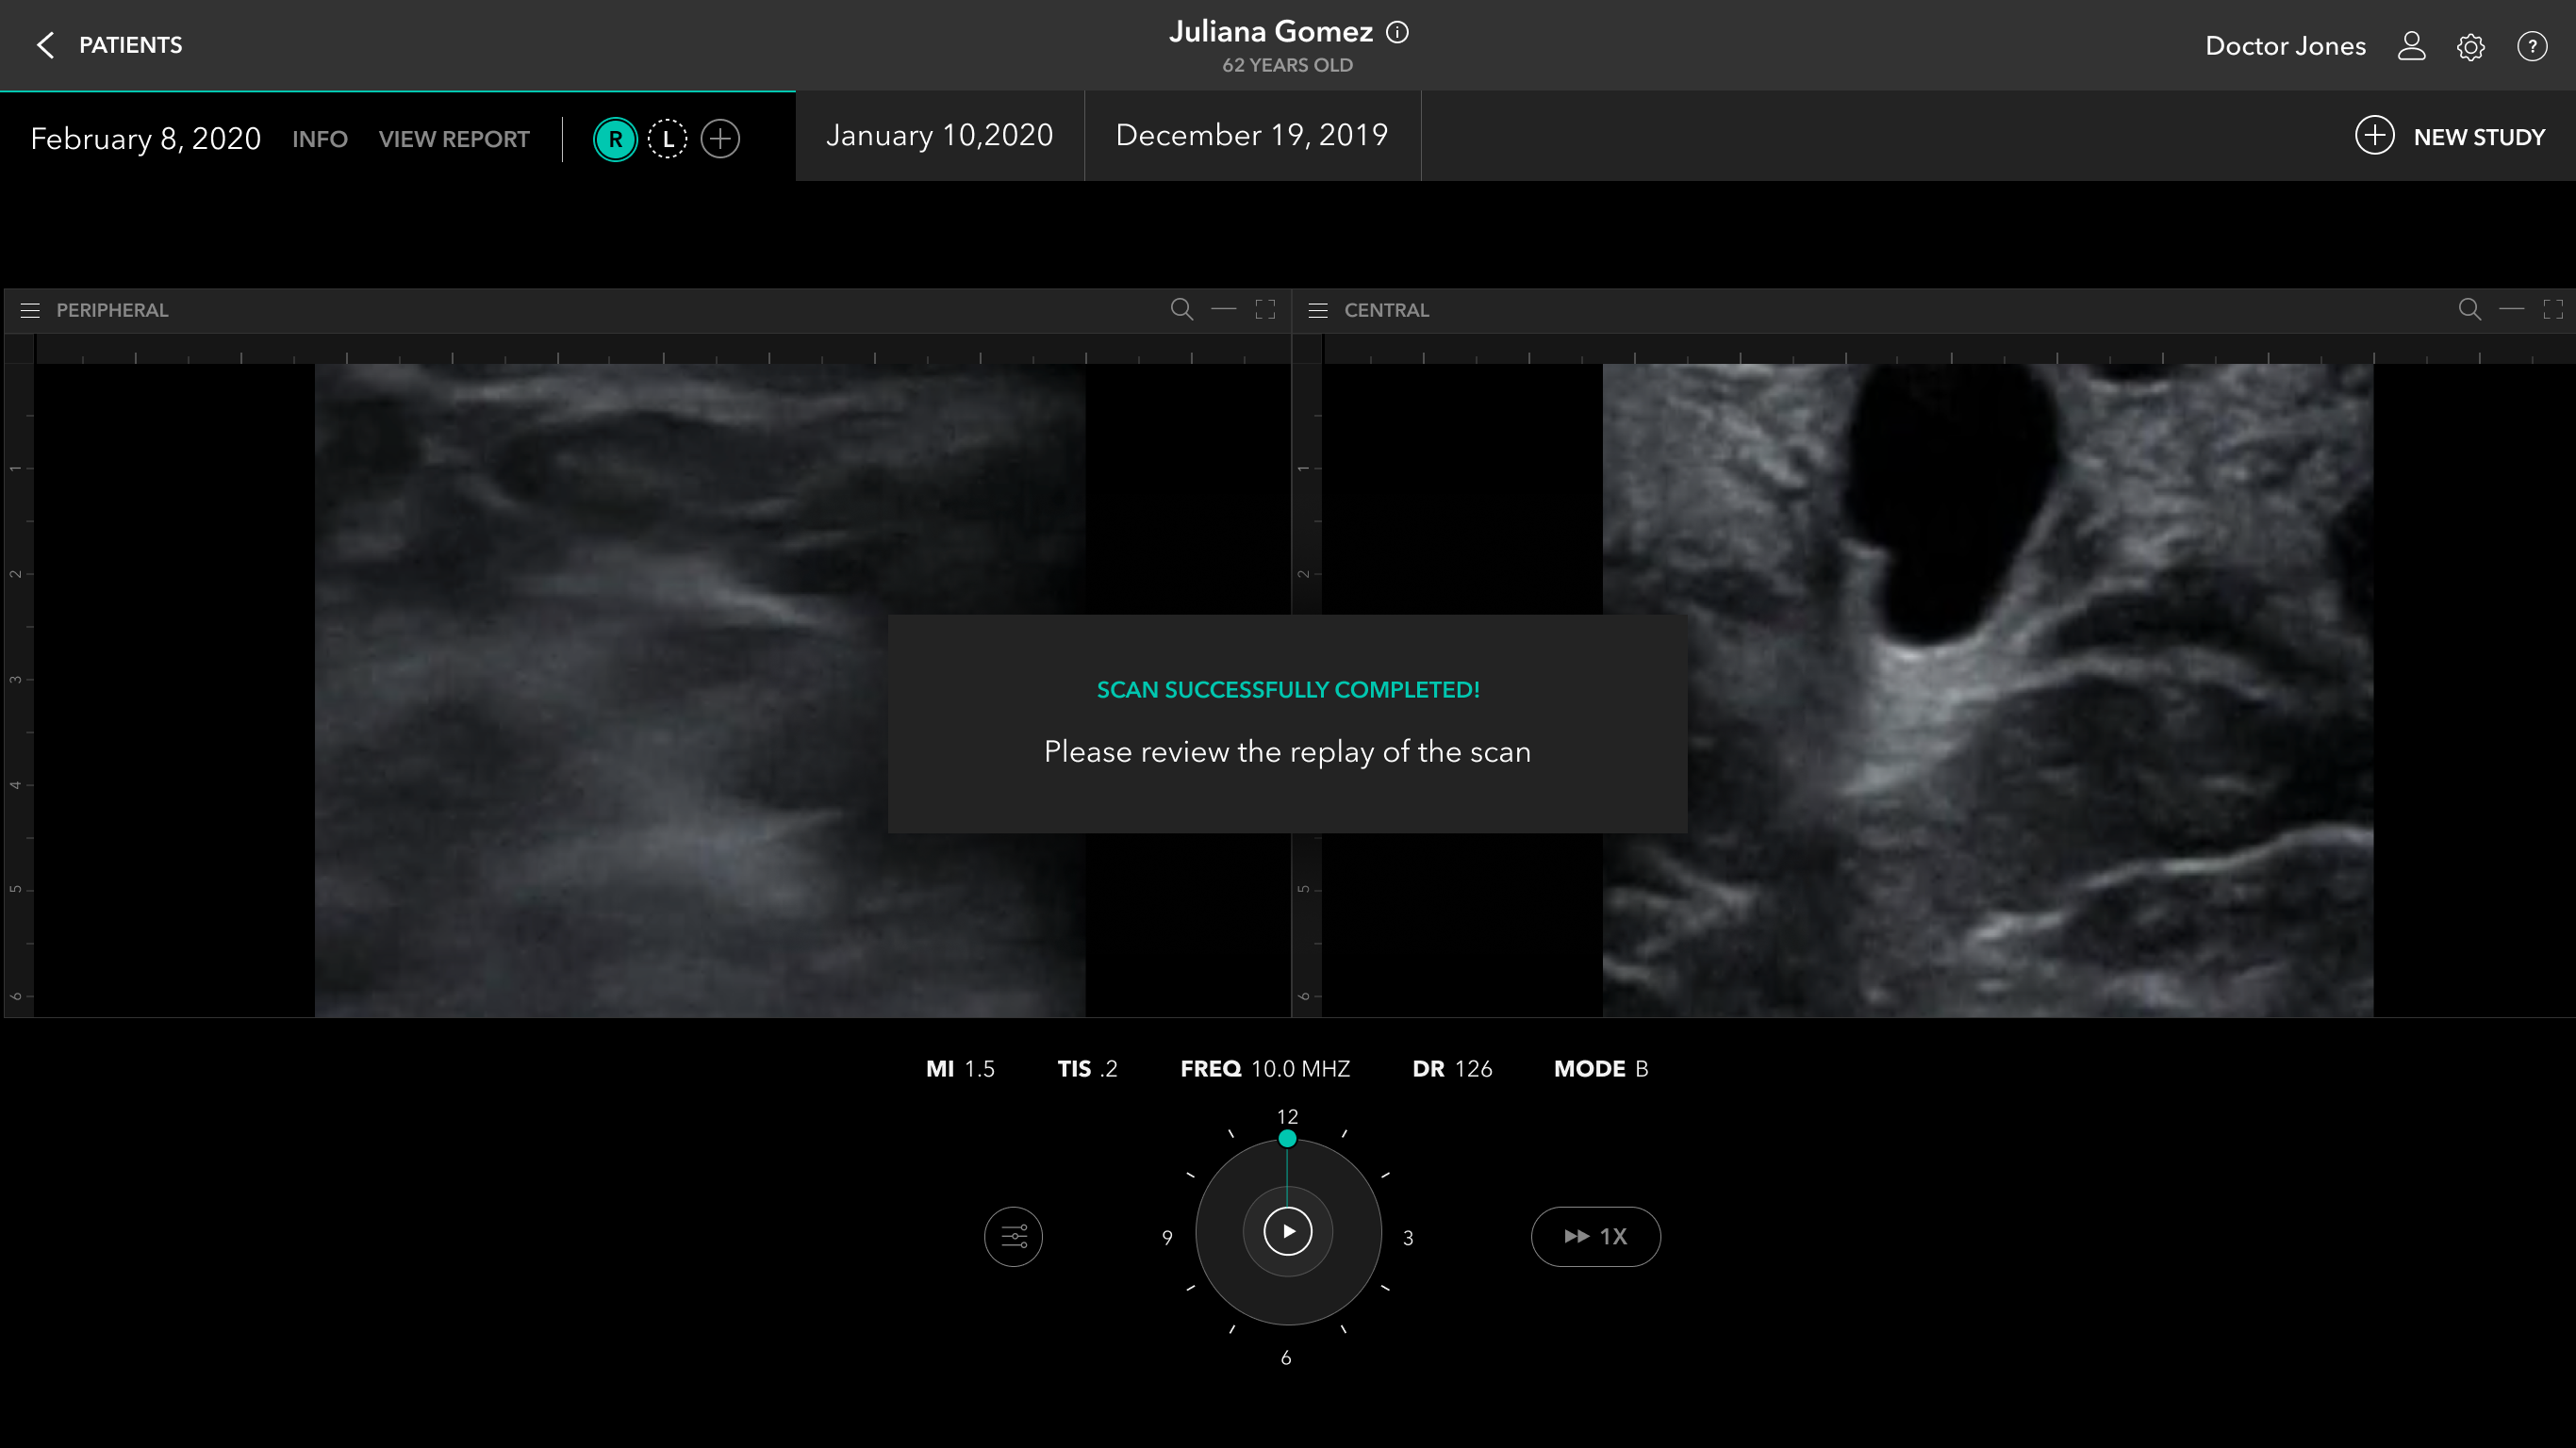

Scan Flow

Post Scan / Labeling And Annotation

Report Creation